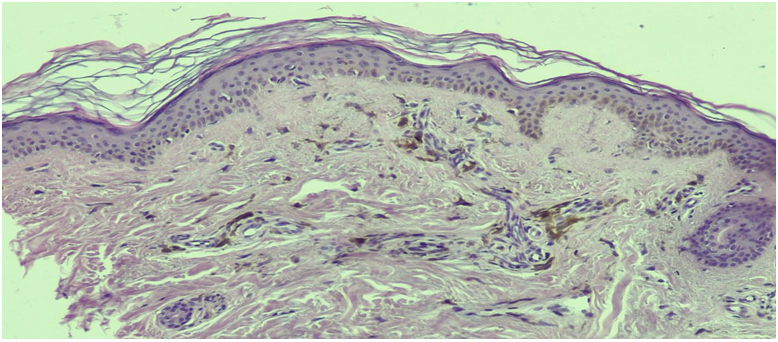

| Figure 1. Diagnosis: persistent dyschromic erythema. The epidermis shows hyperpigmentation and vacuolar degeneration of the basal layer. In the dermis, a perivascular lymphocytic-histiocytic infiltrate with a large number of melanophages is observed. Hematoxylin and eosin staining. Magnification x100 |

Comparison of our observations with recent publications demonstrates: persistent dyschromic erythema is characterized by high levels of CD68-positive macrophages and negative HMB-45, which corresponds to a pattern of secondary pigmentation without active melanogenesis. The near-complete loss of MART-1/MITF+ cells (< 1 cell·mm−1) in hypopigmented areas confirms the vitiligo-like component. For progressive macular hypomelanosis, it is recommended to supplement the study with PCR identification of Cutibacterium acnes subsp. elongatum, as shown in the work of McDowell et al. (2021).